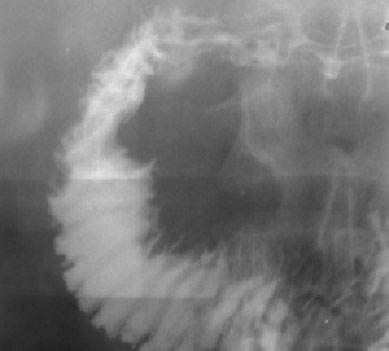

Signo de esclerodermia en el tránsito intestinal. Describe un acercamiento de las válvulas conniventes, que conservan el grosor normal, debido a dilatación de la luz intestinal (flechas blancas). Se afecta con más frecuencia el yeyuno y el íleon proximal. Este hallazgo se debe a la afectación de las capas musculares de las asas intestinales en la esclerodermia.

Semiológicamente este signo es similar al anterior, el Signo de las pilas de monedas, aunque el nombre de Signo del intestino enjuto es exclusivo de la esclerodermia.

Resulta difícil la traducción del nombre original en inglés de este signo (hide-bound bowel). En sentido figurado hide-bound significa rígido, estricto, términos que no se ajustan al aspecto de las asas en la esclerodermia. El término está tomado de la descripción de la apariencia de la piel en esta enfermedad, que se encuentra engrosada, endurecida y adherida a planos profundos, y se compara a la piel gruesa de animales domésticos como la vaca o el caballo, pegada al hueso.

El arículo de referencia es: Perry J. Pickhardt. The «hide-bound» bowel sign. Radiology 1999; 213:837-838. En: http://pubs.rsna.org/doi/full/10.1148/radiology.213.3.r99dc21837.